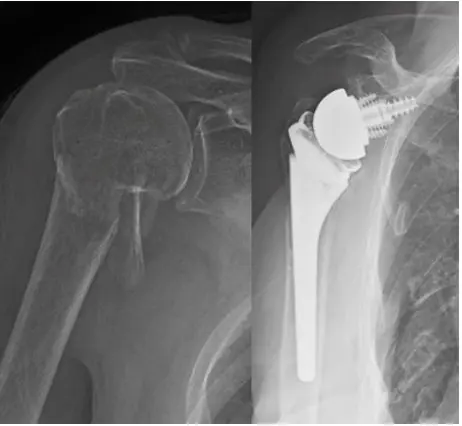

Total Shoulder Replacement

Total shoulder replacement is a reliable option for patients with severe arthritis who have exhausted all non-operative options including physical therapy, injections and pain medication.

In addition to his experience with elective total shoulder replacement, Dr Schultz completed a dedicated orthopedic traumatology fellowship at the University of Texas Health Science Center in Houston, where he also gained valuable experience doing shoulder replacements in patients with proximal humerus fractures. This extra training gives him a unique perspective and skill set to treat complex shoulder and proximal humerus fracture as well as fractures are total shoulder replacements (periprosthetic fractures)

Types of Shoulder Replacement

- Anatomic Total Shoulder Replacement – replaces the ball and the socket in their normal position. This is an option in patients with shoulder arthritis and a functioning rotator cuff tendon.

- Reverse Shoulder Replacement – used when the rotator cuff is badly damaged or in the setting of proximal humerus fractures. During this procedure, the positions of the ball and socket are switched, changing the biomechanics of the shoulder to allow for improved motion and function.

The Procedure

During this surgical procedure, damaged bone and cartilage are removed and then replaced with metal and plastic implants that resemble the shape of the shoulder and allow similar movement. More Info.

Recovery

Patients typically can go home the same day or stay in the hospital for one night. Their arm is placed in a sling, and physical therapy is recommended shortly thereafter to help restore strength and mobility. Initial recovery takes about six to eight weeks. However, full recovery may take several months.

Risks and Benefits

Shoulder replacement can provide significant pain relief and improve arm function. However, like all surgeries, it carries risks such as infection, implant loosening, dislocation, nerve injury, or stiffness.